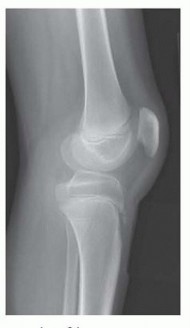

Radiographic Templating and EUA

High-quality, standardized radiographs are mandatory. A true lateral radiograph of the knee, obtained with the patient supine and the knee forced into maximum extension (often utilizing a bolster under the ankle or distal tibia), is critical for measuring the true bony fixed flexion deformity. This angle dictates the size of the extension wedge to be removed. Patellar height is quantified using the Insall-Salvati ratio or the Koshino index to plan the exact distance of distal advancement required. Long-leg alignment films are scrutinized for any coronal plane deformities (varus or valgus) that must be corrected simultaneously.